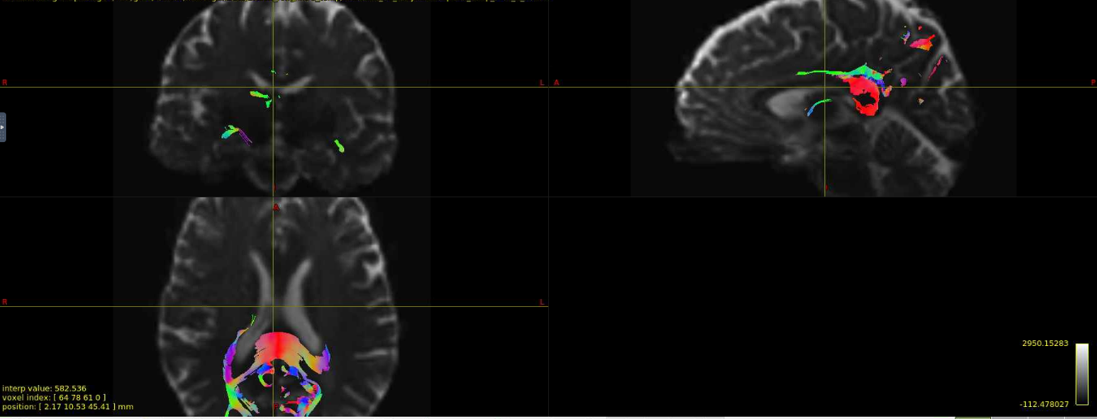

Interesting… From the coronal slices it seems like there are other WM regions devoid of tracks, such as the uncinate fasciculus. The missing part of the corpus callosums suggests that the tapetum is missing, too, which also goes to the temporal lobe. There may be something off in the diffusion data in the temporal lobes. What happens if you seed the missing region in the corpus callosum?

Thanks for your response! If I seed from the missing regions, I still see a similar pattern. I’ve also tried changing the -angle option from the default to 70 and 80, and the -step option to .2 and .08, and the same pattern persists. Since my CSD data looks normal, I’m thinking that maybe the tensor algorithm is undertracking certain regions.

It’s hard to tell from the small images, but it seem counterintuitive that a seed region would have zero streamlines going through it… unless the underlying data does not support a streamline. Can you post an image of your FA map and zoom in the callosum? Maybe there is a big hole of FA values in that region.

Yes, I can post the FA maps! I also thought that it was weird that there were no streamlines from the corpus callosum, but the FA maps look okay.